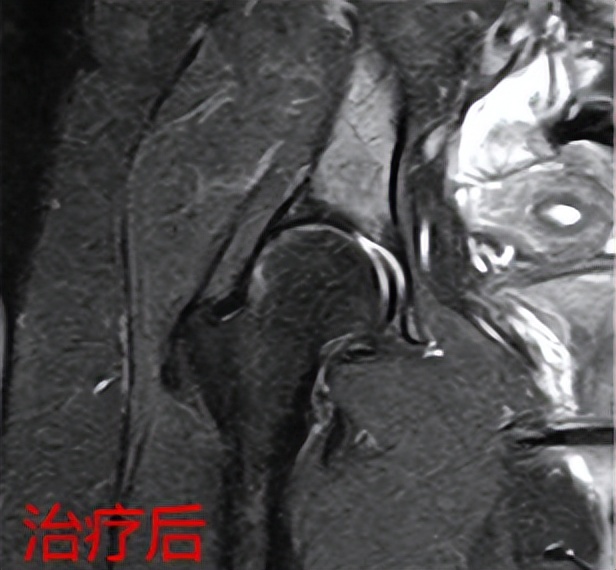

股骨头水肿综合症

患者孙某,女性,65岁,1个月前出现右下肢疼痛,伴有活动受限并有放射痛,到当地医院多方求治都考虑腰椎间盘突出症,给予对症治疗,但孙某右下肢疼痛不见好转,反而逐渐加重,夜间疼痛严重时无法入睡,生活痛苦不堪,家属经多方打听找到骨病·骨肿瘤科I王顺利主任,经过详细细微的查体,王顺利主任发现患者右髋部疼痛、活动受限明显,并伴有右下肢放射痛,结合患者已有的影像学检查,考虑股骨头病变引起,给予办理入院手续后,完善髋关节MRI检查后,果不其然是右侧右侧股骨头坏死、股骨头水肿综合征,结合患者年龄大,有高血压、冠心病等内科疾病,采用综合保守治疗,并应用体外聚焦式冲击波治疗,在应用冲击波治疗两次后,右髋部及右下肢疼痛,用孙某的话“奇迹般不疼了”,右髋部活动度恢复,患者及家属都非常感激王主任。一个多月没有看好的疼痛,来到郑州市骨科医院骨病·骨肿瘤科I,治疗两天后,疼痛就好了,非常高兴。王主任再次叮嘱患者,虽然目前疼痛缓解,但疾病还没有好,需要继续治疗,后面经过三个疗程的冲击波治疗,患者孙某右下肢疼痛消失了,恢复行走。